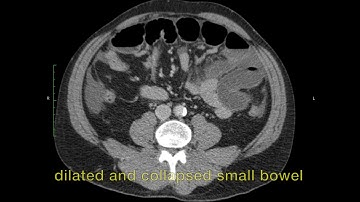

closed loop ct coronal